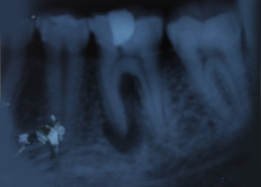

Pre-OP IOPAR

Hemisectomy

Immediate Post-Surgical IOPAR